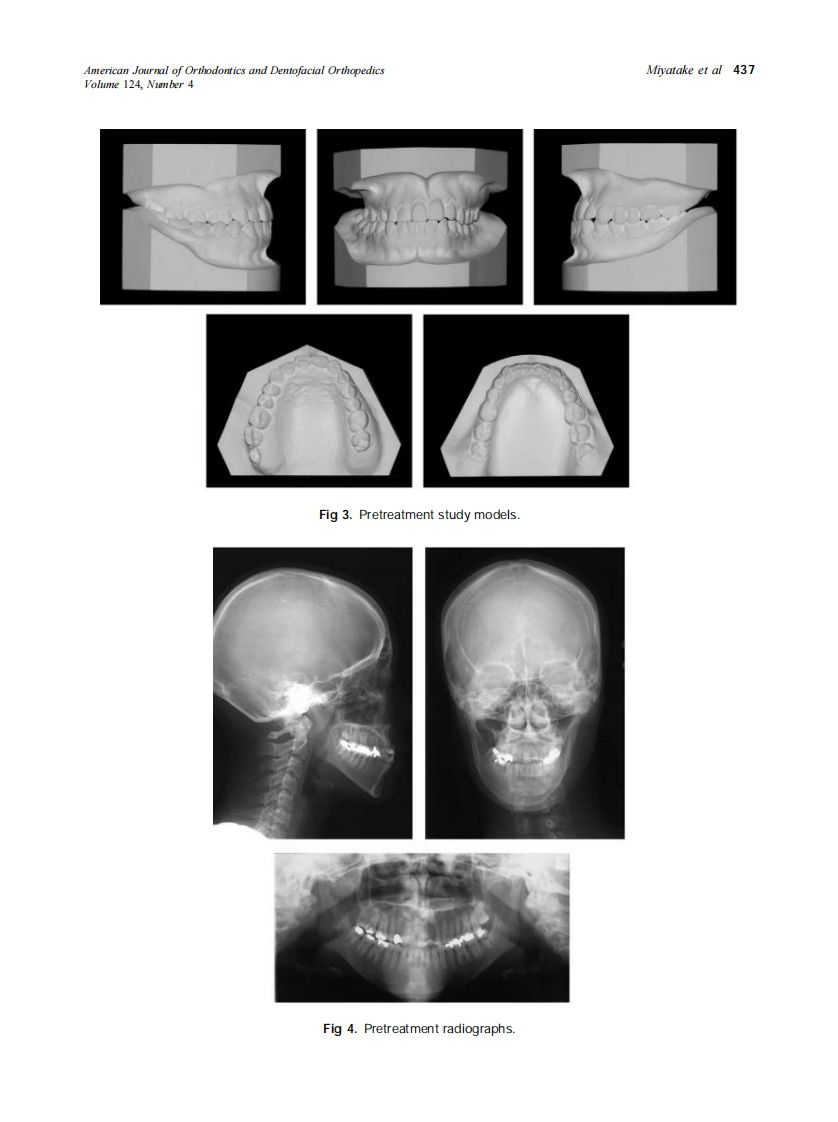

2003_124_4_435_445_Miyatake.pdf